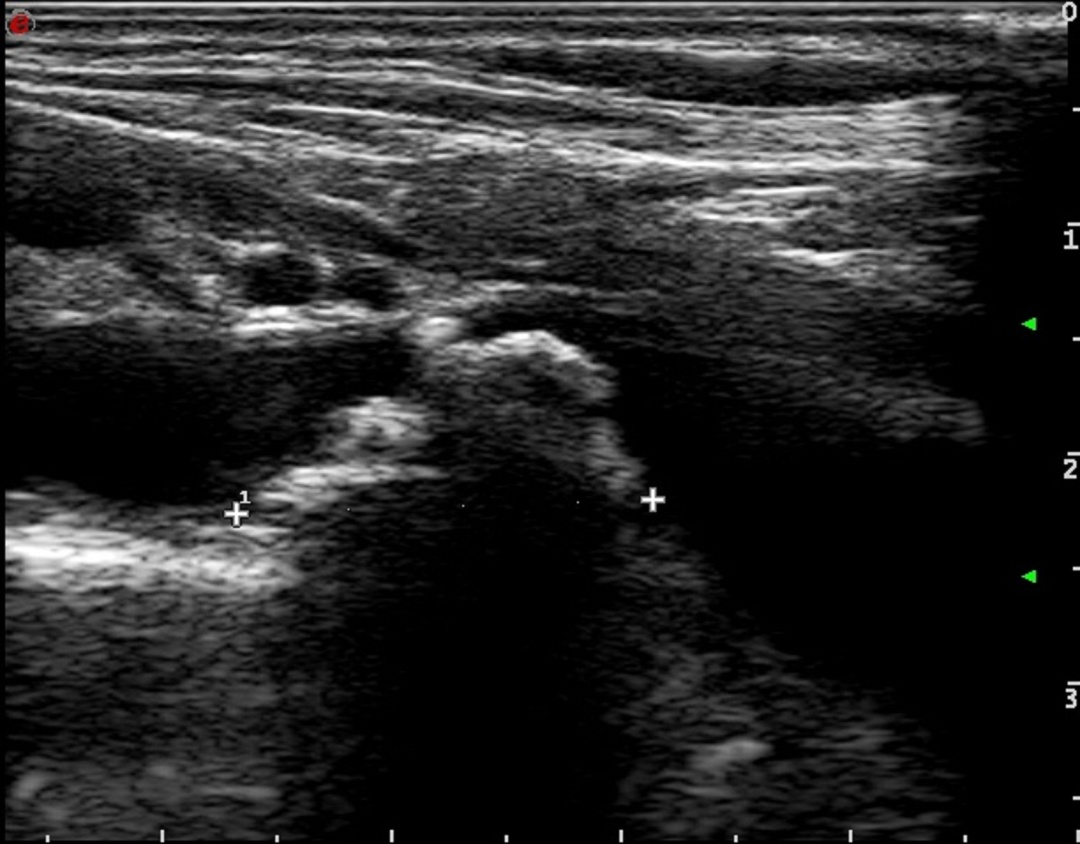

超声诊断科血管疾病超声组陈曦医生通过详细扫查发现,李伯伯右侧锁骨下动脉起始处存在一枚较大斑块,导致血管狭窄率超过50%。同时,其右侧椎动脉起始处存在先天性轻度狭窄,且椎动脉血流方向完全逆转,形成典型的“锁骨下动脉窃血”现象。陈医生解释,由于锁骨下动脉狭窄引发虹吸效应,本应供应脑部的血液逆流至病变血管,导致椎-基底动脉缺血及上肢供血不足,从而引发头晕、视物模糊、上肢乏力等症状。

进一步超声评估显示,李伯伯右侧椎动脉血流频谱在收缩期和舒张期均呈完全反向,确诊为III型完全型窃血。基于这一明确诊断,心血管团队为其实施了锁骨下动脉支架植入术。术后,李伯伯的头晕及上肢无力症状完全消失,血压恢复对称,桡动脉搏动明显增强。医生特别叮嘱他控制运动强度,避免长时间上肢用力,并定期复查血管状况。